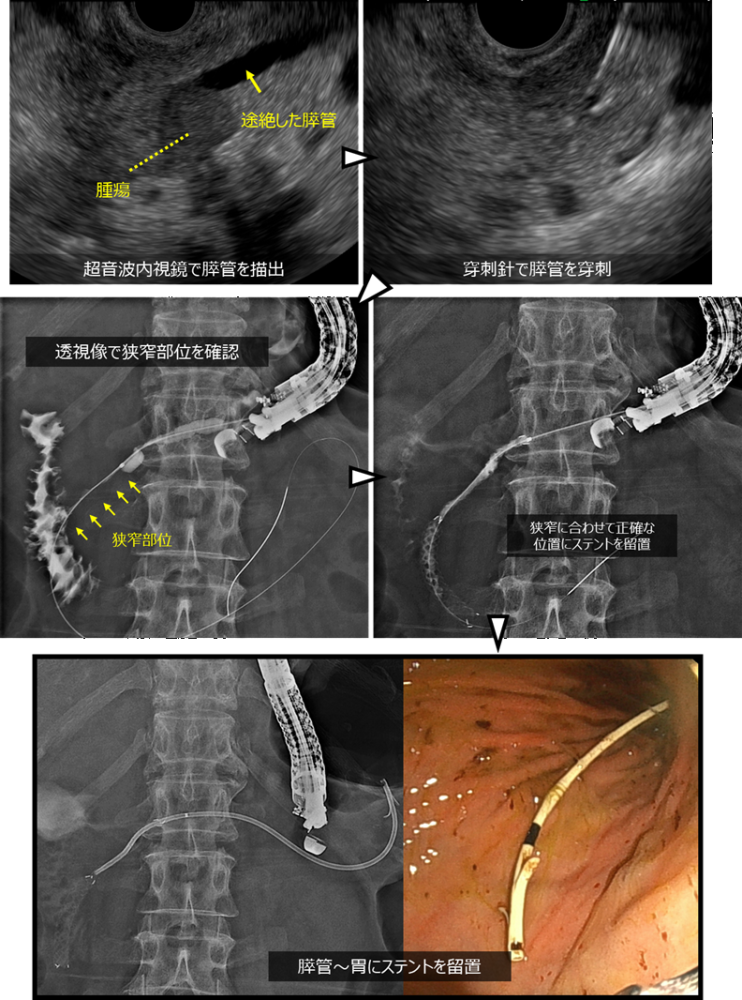

まずERCPによる治療を試みましたが、腫瘍の浸潤により膵管の出口(膵管口)が不明瞭で、膵管へのアプローチが困難でした。そのため、超音波内視鏡下膵管ドレナージ(EUS-PD)へ治療を変更しました。

超音波内視鏡を用いて胃の内側から膵管を穿刺し、膵管内に順行性に乳頭側へ金属ステントを留置しました。さらに、胃と膵管の間に通り道を作るためにプラスチックステントを留置し、膵液の流れを確保しました。

治療後は膵炎症状が改善し、全身状態も回復して退院となりました。